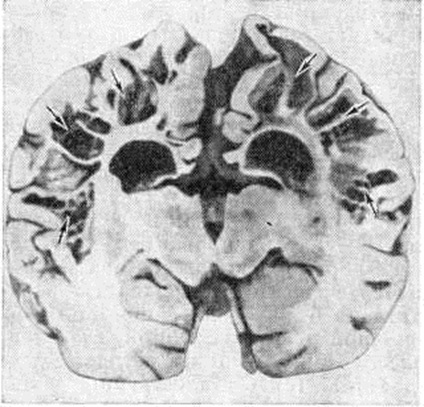

Рис. 1.

Макропрепарат головного мозга при истинной порэнцефалии (фронтальный разрез): внутримозговая кистозная полость (указана стрелками), сообщающаяся с боковым желудочком и поверхностью полушария головного мозга.

Различают истинную и ложную Порэнцефалия При истинной Порэнцефалия кисты могут сообщаться с желудочками мозга, являясь как бы их дивертикулами, иногда распространяющимися до наружной поверхности полушария головного мозга (рисунок 1). Реже кистозные полости с желудочками мозга не сообщаются. Величина кист очень вариабельна; некоторые из них иногда могут занимать половину и более половины полушария головного мозга, Внутренняя поверхность кисты чаще всего гладкая, выстлана эпендимоподобной оболочкой. Если киста сообщается с желудочками мозга, она содержит цереброспинальную жидкость, а если не сообщается — кистозную желтоватую жидкость с большим количеством белка, Микроскопически в стенке кисты выявляются участки, образованные гетеротопированной, имеющей неправильное строение корой головного мозга. В стенках кист иногда обнаруживают гемоглобиногенную пигментацию (следы очаговых кровоизлияний) и мелкие аноксические некрозы. Боковые желудочки часто имеют неправильную форму и расширены, особенно в области прилегания порэнцефалической кисты. Извилины полушарий головного мозга радиально погружены в направлении кисты, а иногда в этой области совсем отсутствуют и на их месте имеется лишь тонкая пластинка из мозгового вещества и мягкрй оболочки головного мозга, кратерообразно западающая при вскрытии полости. Гистологический изменения в ближайших к кисте извилинах головного мозга характеризуются выраженным разрежением ганглиозных клеток и неправильной ориентировкой клеточных слоев. В мягкой оболочке головного мозга отмечаются очаговые некрозы. Эти изменения указывают на раннее возникновение истинной Порэнцефалия